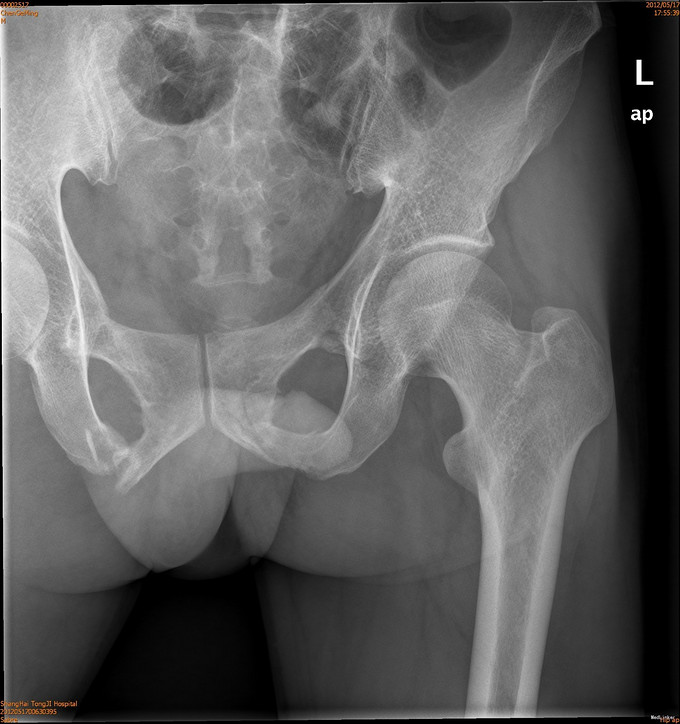

患者男,41岁,因车祸致双侧髂腰部、中下腹部及会阴部疼痛,伴尿道出血1小时。患者于1小时前不慎被汽车撞伤,当即感到双侧髂腰部、中下腹部及会阴部剧痛,尿道口有鲜血渗出,有昏迷,后自行苏醒,120送入我院急诊,CT示两侧骶髂关节前缘骨折,双侧耻骨上下支骨折,周围血肿形成。急诊导尿失败,遂入院治疗。

诊断为耻骨上下支骨折,兄弟科室会诊治疗结束后,患者病情稳定,行切开复位内固定术。